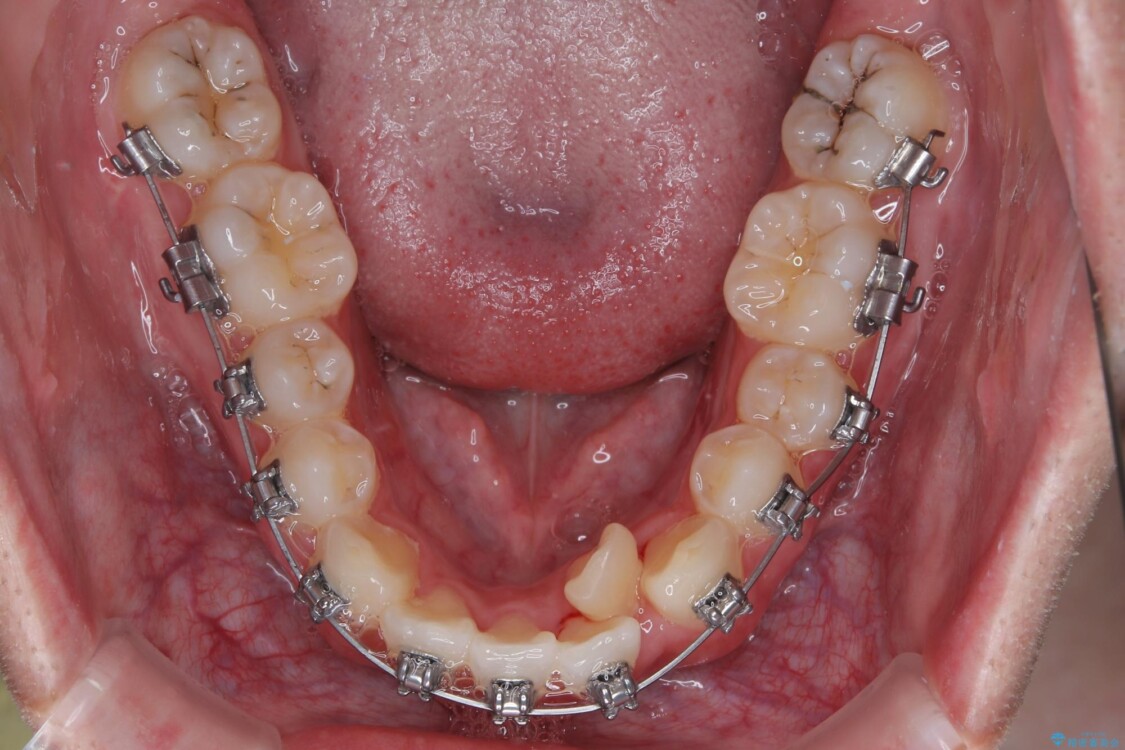

このような歯列の狭さに起因するデコボコを改善するために、**MARPE(骨に固定する上顎急速拡大装置)**を使用して、上顎の横幅を拡大し、これにより歯が並ぶためのスペースを確保し、メタルブラケットを用いて歯列を整えていく計画としました。

治療途中

• 1年でここまで変わる!歯列のがたつきと正中のズレを改善した矯正治療(メタルブラケット×MARPE) 治療途中画像